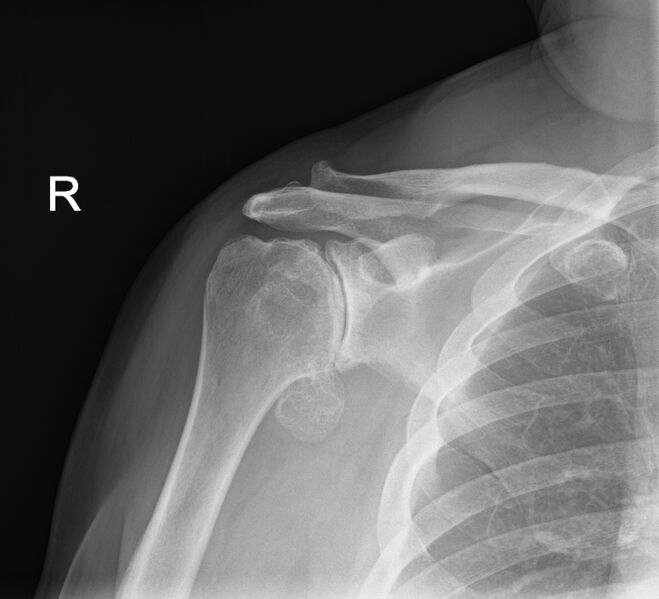

Before going down the path of receiving treatment for your frozen shoulder, it is really important to obtain an accurate diagnosis. Some conditions, particularly sinister pathologies can masquerade as a frozen shoulder. Our Action Rehab therapists are trained in early detection of frozen shoulder and will be able to refer and interpret your scans to help you decide on an appropriate treatment plan.

Choosing the right hand Therapist starts with them being able to read your X-rays and then fabricate the right brace for you. The therapists at Action Rehab are experienced in assessing and reading X-rays.